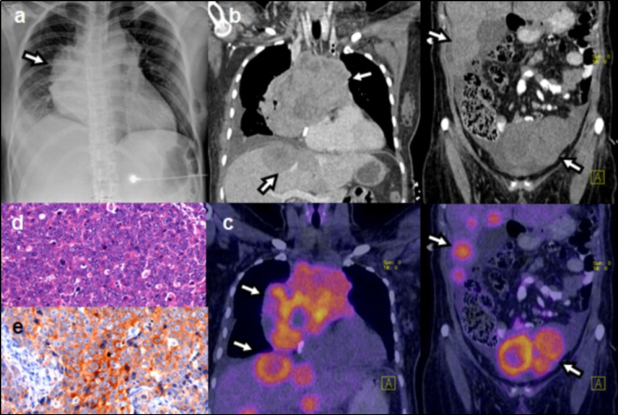

El ID calculado considerando los pacientes con etiología maligna confirmada mediante biopsia o seguimiento, arrojó un valor de 47%. La proporción de FP tomando en cuenta aquellos pacientes con al menos un hallazgo positivo en el PET-CT con otra etiología confirmada que no fuera maligna y aquellos en los cuales no fue posible determinar el tipo de etiología mediante biopsia o seguimiento, fue de 27%. De los pacientes en los que se encontró una etiología maligna, 49 casos fueron confirmados mediante biopsia y 1 mediante seguimiento. De los pacientes con biopsia, el diagnóstico de anatomía patológica más frecuente fue el adenocarcinoma pobremente diferenciado (tabla 1). En cuanto a localización, el sitio primario más común fue el pulmón, seguido del páncreas (tabla 2). Las figuras 1-4 ilustran algunos casos representativos de nuestra serie.